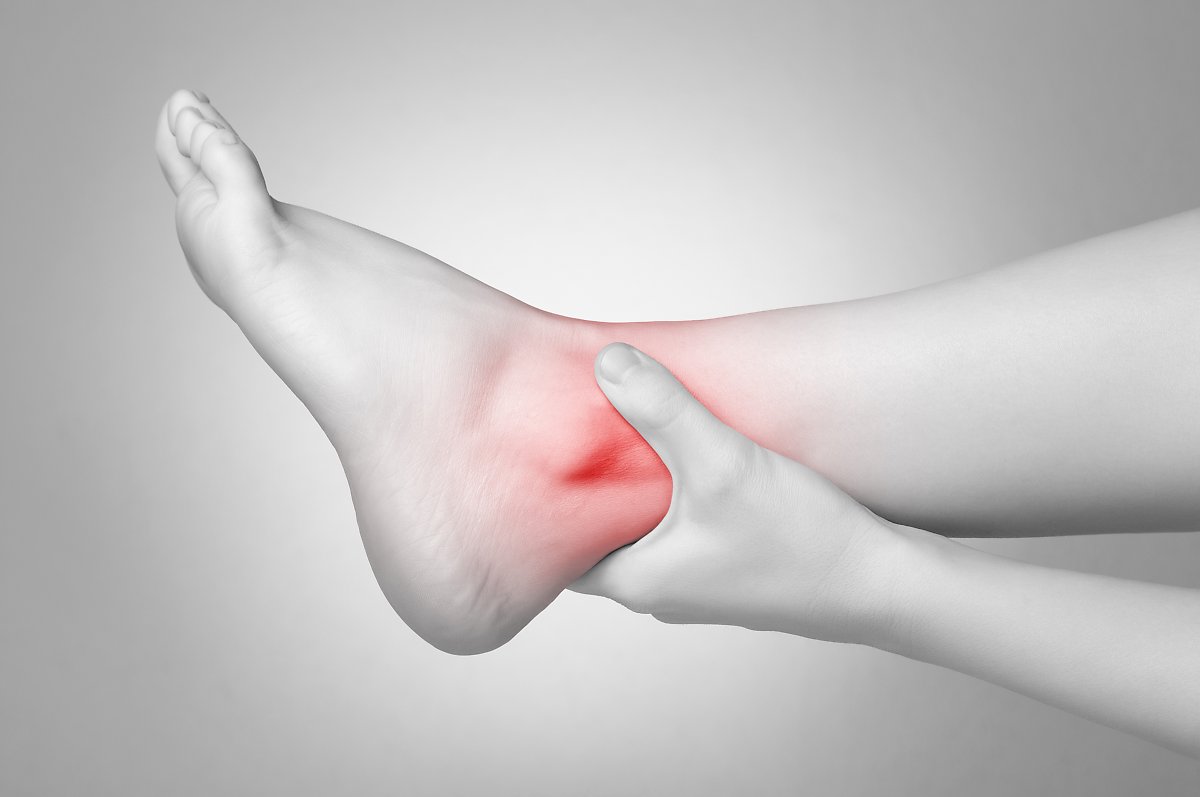

발목 염좌의 증상

발목의 통증과 부종, 발목을 만졌을 때 통증이 느껴지는 압통 등이 발목 염좌의 대표적인 증상입니다. 심한 경우에는 서 있기도 힘들 정도의 통증을 느끼며, 시간이 흐르면서 발목 안쪽이나 바깥쪽에 멍이 생기기도 합니다.